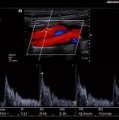

ACUSON P500 Ultrasound System

●可攜式超音波儀器隨時隨地提供高品質影像成像

●提供更有效率的臨床經驗